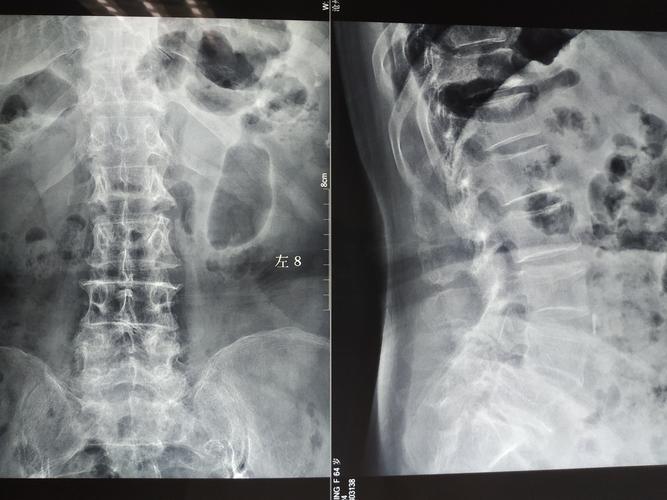

腰椎4一5节滑脱图

腰椎4一5节滑脱图,腰椎滑脱1度图片

腰椎滑脱症综述附图解

腰椎滑脱1度图片

腰椎滑脱图片示意图

腰椎滑脱一二三四度图

腰椎滑脱的图片

腰椎滑脱图片

腰椎滑脱图片怎么看